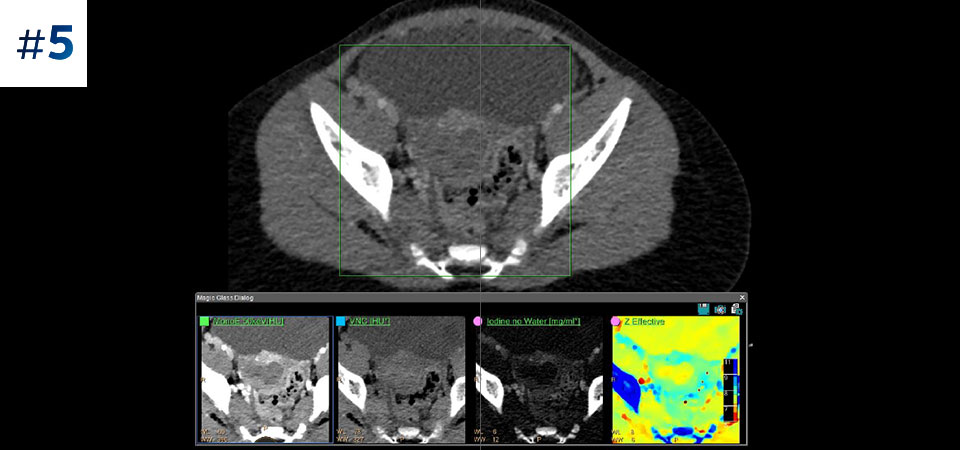

Pacjenci o różnych typach budowy ciała Możliwość przeprowadzania badań u pacjentów różnej wielkości, od dzieci po osoby otyłe.

Ograniczenie liczby ponownych badań Udoskonalona charakterystyka i wizualizacja tkanek może ograniczyć konieczność wykonywania ponownych badań, jaka zachodzi w przypadku badań o niezadowalającej jakości oraz przypadkowych obserwacji.

Nie ograniczaj się do konwencjonalnej tomografii komputerowej. Zobacz, jak wyniki uzyskane dzięki warstwom detektora spektralnego mogą zwiększyć pewność diagnostyczną.

Zobacz jak tomograf spektralny pomaga w diagnostyce pacjentów onkologicznych.